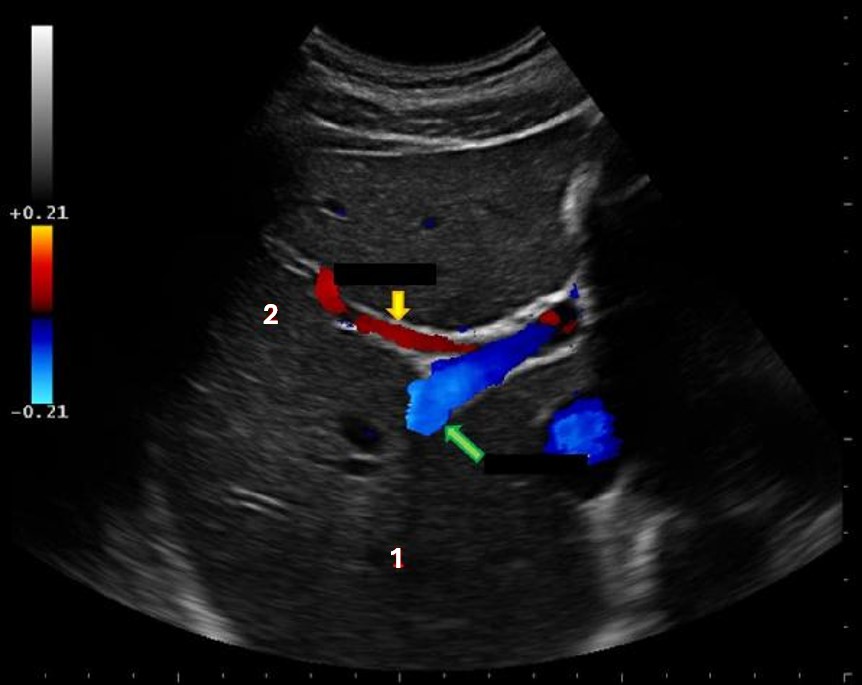

what liver vessels indicated by the yellow arrow?

Anterior right portal vein

What structure is indicated by the yellow arrow?

Main lobar fissure

What structure is indicated by the green arrow?

Main portal vein